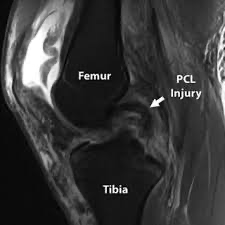

The Posterior Cruciate Ligament (PCL) is one of the main ligaments inside the knee joint. It connects the thigh bone (femur) to the shin bone (tibia) and helps keep the knee stable. The PCL mainly prevents the shin bone from moving too far backward. Injury to the Posterior Cruciate Ligament Injury can affect normal knee movement and stability.

The PCL prevents the shin bone from moving backward, while the ACL prevents it from moving forward. PCL injuries often result from a direct blow to the front of the knee.